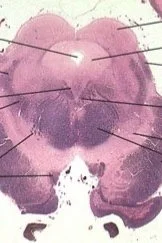

Craniology 06 (First six cranial nerves)

• Descriptive and functional anatomy of the First 6 cranial nerves (I, II, III, IV, V, VI).

• Physiology of the first 6 cranial nerves.

• Pathologies and diagnostic tests of the first 6 cranial nerves.

• Practical techno-methodology of the normalizations of the first 6 cranial nerves.